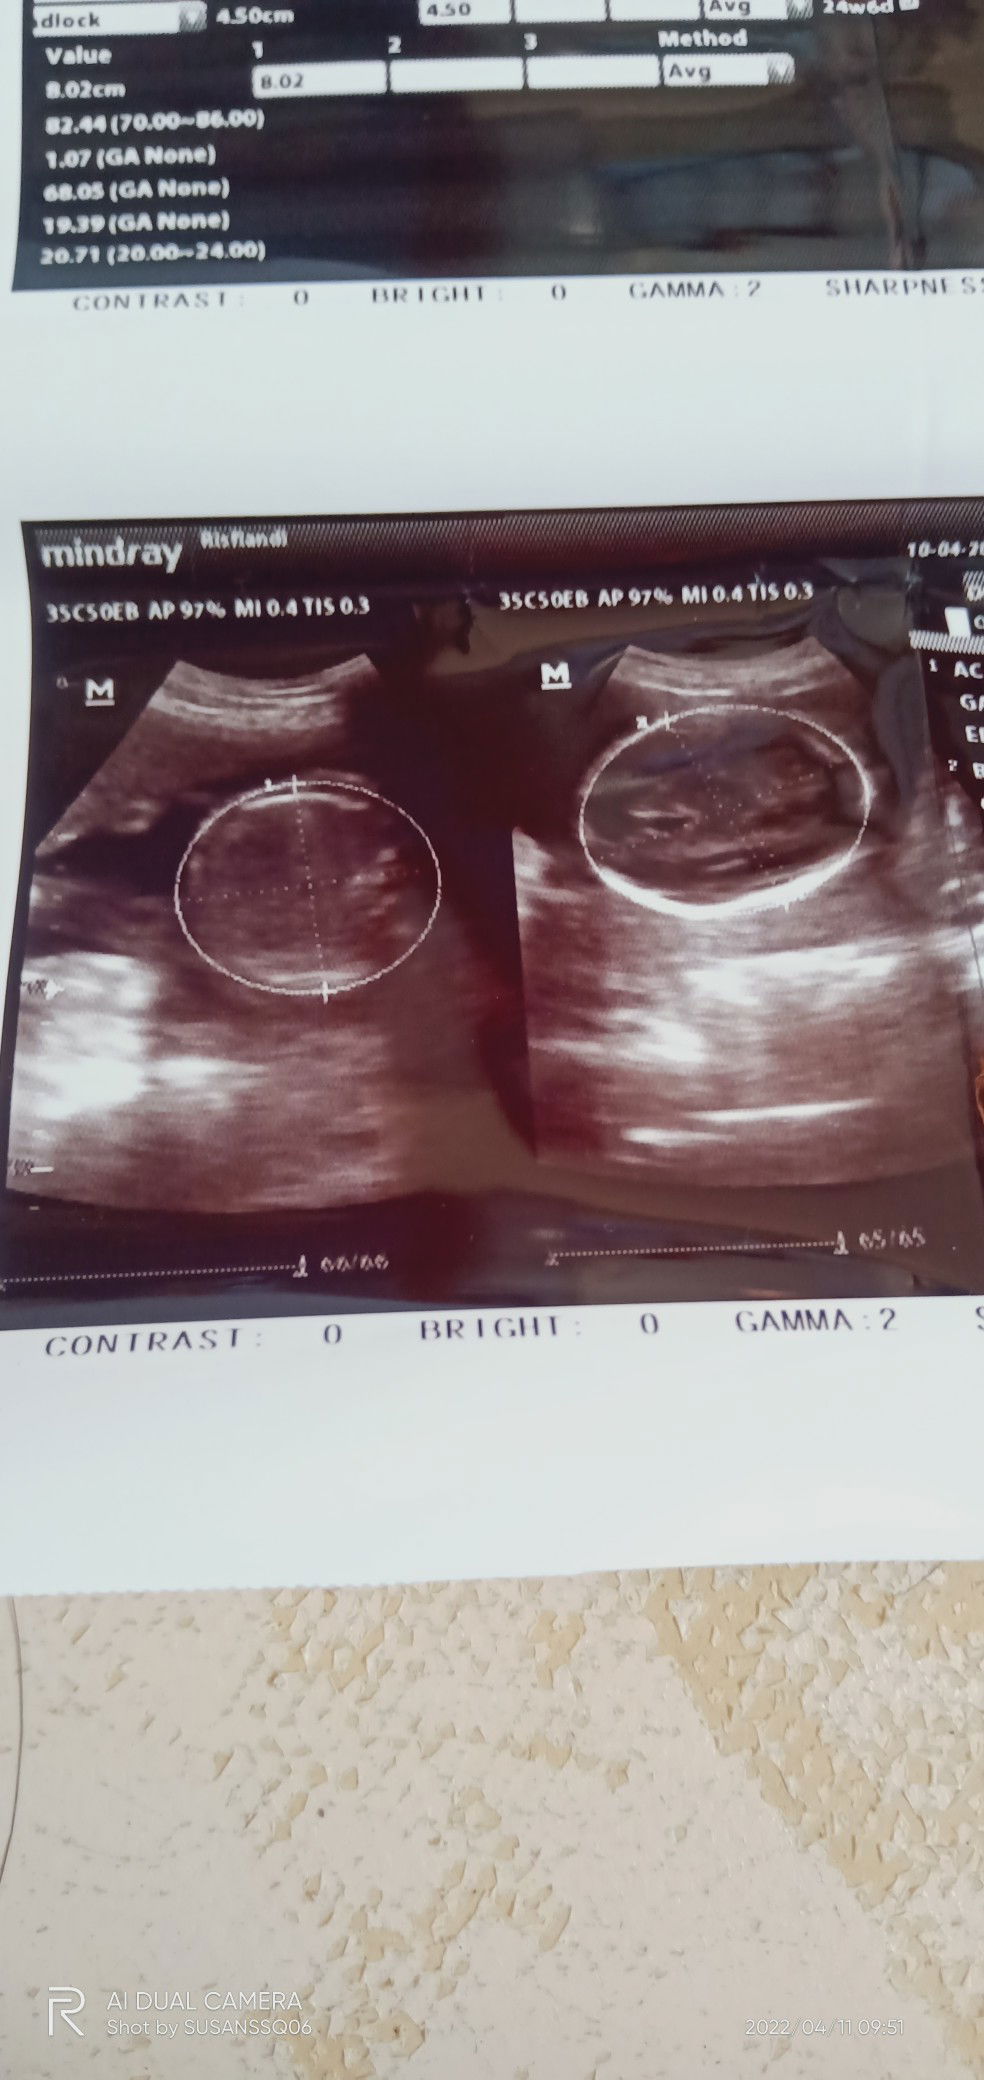

Aku udah memasuki kehamilan 24mnggu , baru ketahuan kemarin , 24 mnggu kebelakang nggak ada keluhan apapun , sering naik motor dan pergi2 jauhh , pas udah ketahuan , malah sering kerasa keluhan nya😊 alhamdulillah bayi nya kuat , ga sampe kenapa2 ,